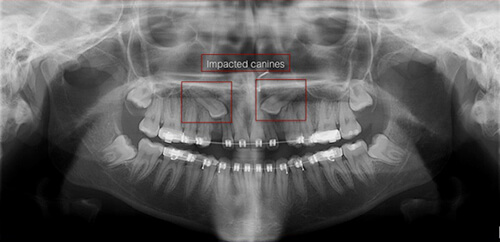

An impacted tooth simply means that it is “stuck” and cannot erupt into function. Patients frequently develop problems with impacted third molar (wisdom) teeth. These teeth get “stuck” in the back of the jaw and can develop painful infections among a host of other problems (see Impacted Wisdom Teeth under Procedures). Since there is rarely a functional need for wisdom teeth, they are usually extracted if they develop problems. The maxillary cuspid (upper eyetooth) is the second most common tooth to become impacted. The cuspid tooth is a critical tooth in the dental arch and plays an important role in your “bite”. The cuspid teeth are very strong biting teeth and have the longest roots of any human teeth. They are designed to be the first teeth that touch when your jaws close together so they guide the rest of the teeth into the proper bite.

These basic principals can be adapted to apply to any impacted tooth in the mouth. It is not that uncommon for both of the maxillary cuspids to be impacted. In these cases, the space in the dental arch form will be prepared on both sides at once. When the orthodontist is ready, the surgeon will expose and bracket both teeth in the same visit so the patient only has to heal from surgery once. Because the anterior teeth (incisors and cuspids) and the bicuspid teeth are small and have single roots, they are easier to erupt if they get impacted than the posterior molar teeth. The molar teeth are much bigger teeth and have multiple roots making them more difficult to move. The orthodontic maneuvers needed to manipulate an impacted molar tooth can be more complicated because of their location in the back of the dental arch.

How are impacted canines diagnosed?

A dentist or orthodontist can diagnose impacted canines through a clinical examination and dental X-rays.